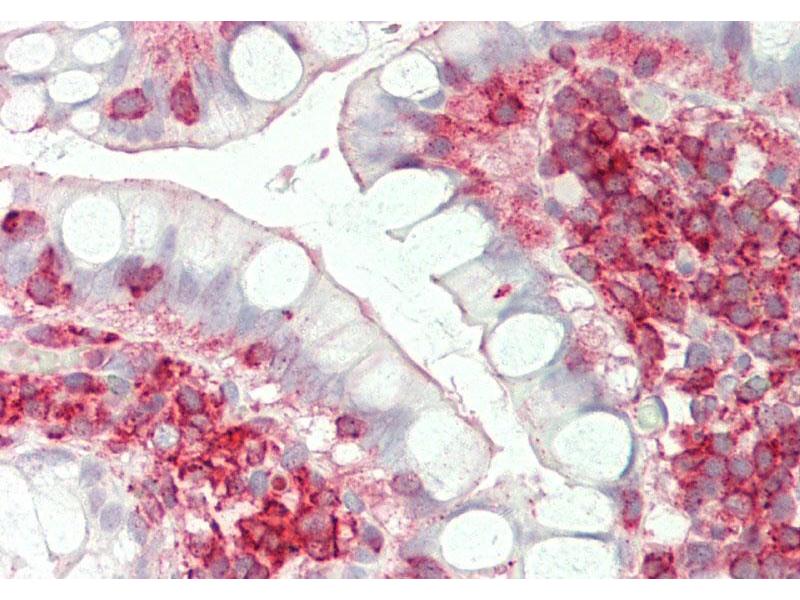

- This is a rabbit polyclonal antibody against ST3GAL4. It was validated on Western Blot and immunohistochemistry.